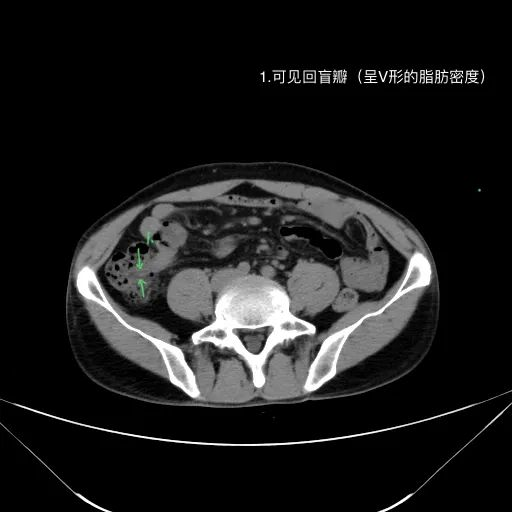

7.胃肠道,特别是胃窦及十二指肠,回盲部及阑尾

肝脏缩小,包膜凹凸不平,肝裂增宽,各叶比例失衡,肝实质密度不均,肝S4小片低密度影,约cm;胆囊不大,其内未见异常密度影,胆道系统未见扩张;胰腺、脾脏形态、密度、大小未见异常;双肾上腺及双肾形态、密度、大小未见异常,双输尿管未见扩张,膀胱充盈良好,壁光滑,其内未见异常密度影;前列腺未见异常;胃肠道未见充盈,壁未见明确增厚,食管胃底多发迂曲、增粗血管,腹部及腹膜后未见肿大淋巴结;腹水。